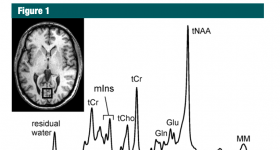

大量已發(fā)表的研究表明,質(zhì)子(氫1 [1H])磁共振(MR)波譜學已從研究工具演變?yōu)榕R床神經(jīng)成像模式。在此,作者總結(jié)了...